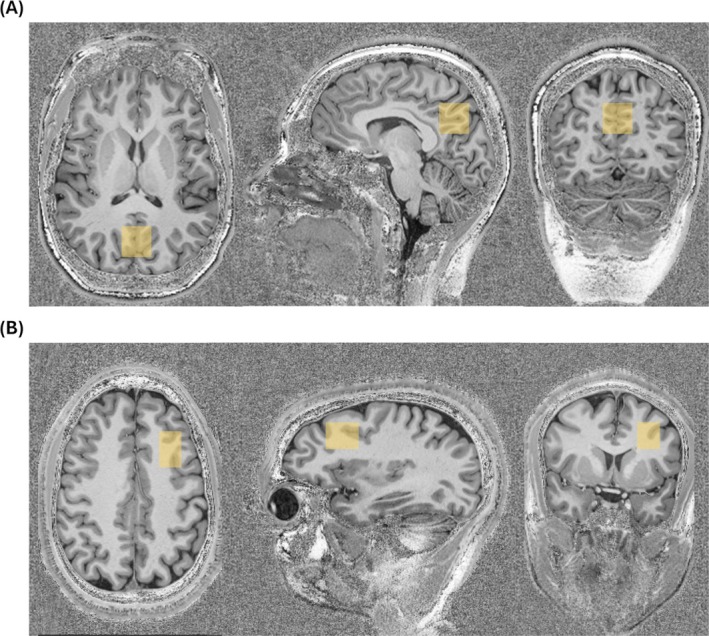

磁共振波谱(MRS)可以实现代谢物的无创定量,但其在体内的应用受到低信噪比(SNRs)和长采集时间的限制。利用超高频(UHF)强度与多通道相控接收阵列相结合可以提高频谱信噪比。使用多通道阵列的一个关键步骤是组合从单个线圈通道获得的光谱。我们之前开发了一种3 T的线圈组合方法,利用秩- r奇异值分解(OpTIMUS)优化截断来整合多通道MRS数据,该方法使用噪声白化的窗口光谱和迭代秩- r奇异值分解(SVD)来组合多通道MRS数据。在这里,我们评估了OpTIMUS在7 T时使用多通道相控阵获得的MR光谱组合,并将光谱信噪比和代谢物量化与使用白化奇异值分解(WSVD)、信噪比平方(S/N2)和布朗方法组合的光谱进行了比较。数据来自14名健康志愿者,包括5名在3岁和7岁时获得数据的志愿者,以及9名艾滋病毒感染者。与其他三种方法相比,使用OpTIMUS的光谱组合获得了更高的信噪比,与我们之前在3t时的结果一致。与使用64个平均值的Brown方法相比,与OpTIMUS结合的光谱具有更高的信噪比,平均次数为平均值的一半(N = 32)。此外,将7 T时使用OpTIMUS组合的光谱与3 T时获得的光谱进行了比较,这些光谱具有相同的平均次数(N = 64)或匹配的采集次数(N = 110次平均),即使在3 T时获得相当的信噪比,光谱拟合也在7 T时得到了持续改善。通过优化光谱线圈组合来提高信噪比和保持光谱质量的能力有可能减少扫描时间,这是MRS常规临床应用的一个关键挑战。

Magnetic resonance spectroscopy (MRS) enables noninvasive quantification of metabolites, but its utility in vivo can be limited by low signal-to-noise ratios (SNRs) and long acquisition times. The use of ultrahigh-field (UHF) strengths (> 3 T) combined with multichannel phased receive arrays can improve spectral SNR. A crucial step in the use of multichannel arrays is the combination of spectra acquired from individual coil channels. We previously developed a coil combination method at 3 T, optimized truncation to integrate multichannel MRS data using rank-R singular value decomposition (OpTIMUS), which uses noise-whitened windowed spectra and iterative rank-R singular value decomposition (SVD) to combine multichannel MRS data. Here, we evaluated OpTIMUS for combination of MR spectra acquired using a multichannel phased array at 7 T and compared spectral SNR and metabolite quantification with spectra combined using whitened SVD (WSVD), signal/noise squared (S/N2), and the Brown method. Data were acquired from 14 healthy volunteers, including five with data acquired at both 3 and 7 T, and from nine people living with HIV. Spectra combined using OpTIMUS resulted in a higher SNR compared to the three other methods, consistent with our prior results at 3 T. With half the number of averages (N = 32), spectra combined with OpTIMUS had higher SNR compared to spectra using the Brown method with 64 averages. Additionally, spectra combined using OpTIMUS at 7 T were compared to spectra acquired at 3 T with the same number of averages (N = 64) or matched acquisition times (N = 110 averages), and spectral fitting was consistently improved at 7 T even when comparable SNR was obtained at 3 T. The ability to increase SNR and maintain spectral quality by optimizing spectral coil combination has the potential to reduce scan time, a key challenge for routine clinical use of MRS.